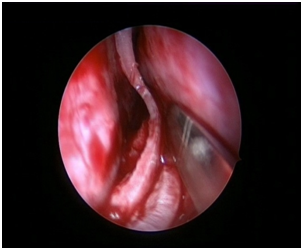

Nasal Endoscopy is done to assess the septal deviation and spurs (Figure 1) ( Figure 2). Septal infiltration is carried out with a solution of 2% Xylocaine with 1: 100,000 adrenaline in the sub-mucosal plane. It is given with a single prick at the inferior most part of the nasal septum at the junction of the septum with the floor of the nasal cavity anterior to the mucocutaneous junction. The infiltration is given at the same point on both the sides (Figure 3). The incision is always given on the deviated side. It is given anterior to the mucocutaneous junction because the skin present at that place is thick and chance of a tear of the flap is less (Figure 4). The mucoperichondrial flap is raised on the deviated side with a Freer’s elevator strictly under vision. The flap is not to be raised beyond the deviated part because the part of the septum posterior to the deviation is not under direct vision (Figure 5) (Figure 6). The caudal end of the septum is then palpated and an incision is given on the cartilage 1cm behind the columella. This 1cm of the cartilage is saved to prevent post operative tip deformities (Figure 7). The cartilage is sliced and the opposite side is entered, the mucoperichondrial flap of the opposite side is then elevated with a Freer’s elevator. A cut is given in the septal cartilage as high as possible. A septal window is created and a Ballenger’s swivel knife is taken and lodged in the place where the cartilage was cut. Creation of a septal window thus increases the area of exposure (Figure 8) (Figure 9). The flap on the non-deviated side is elevated till the bony-cartilaginous junction.

Figure 1 Deviation of septum to left side.

Figure 2 Spur present towards left side.